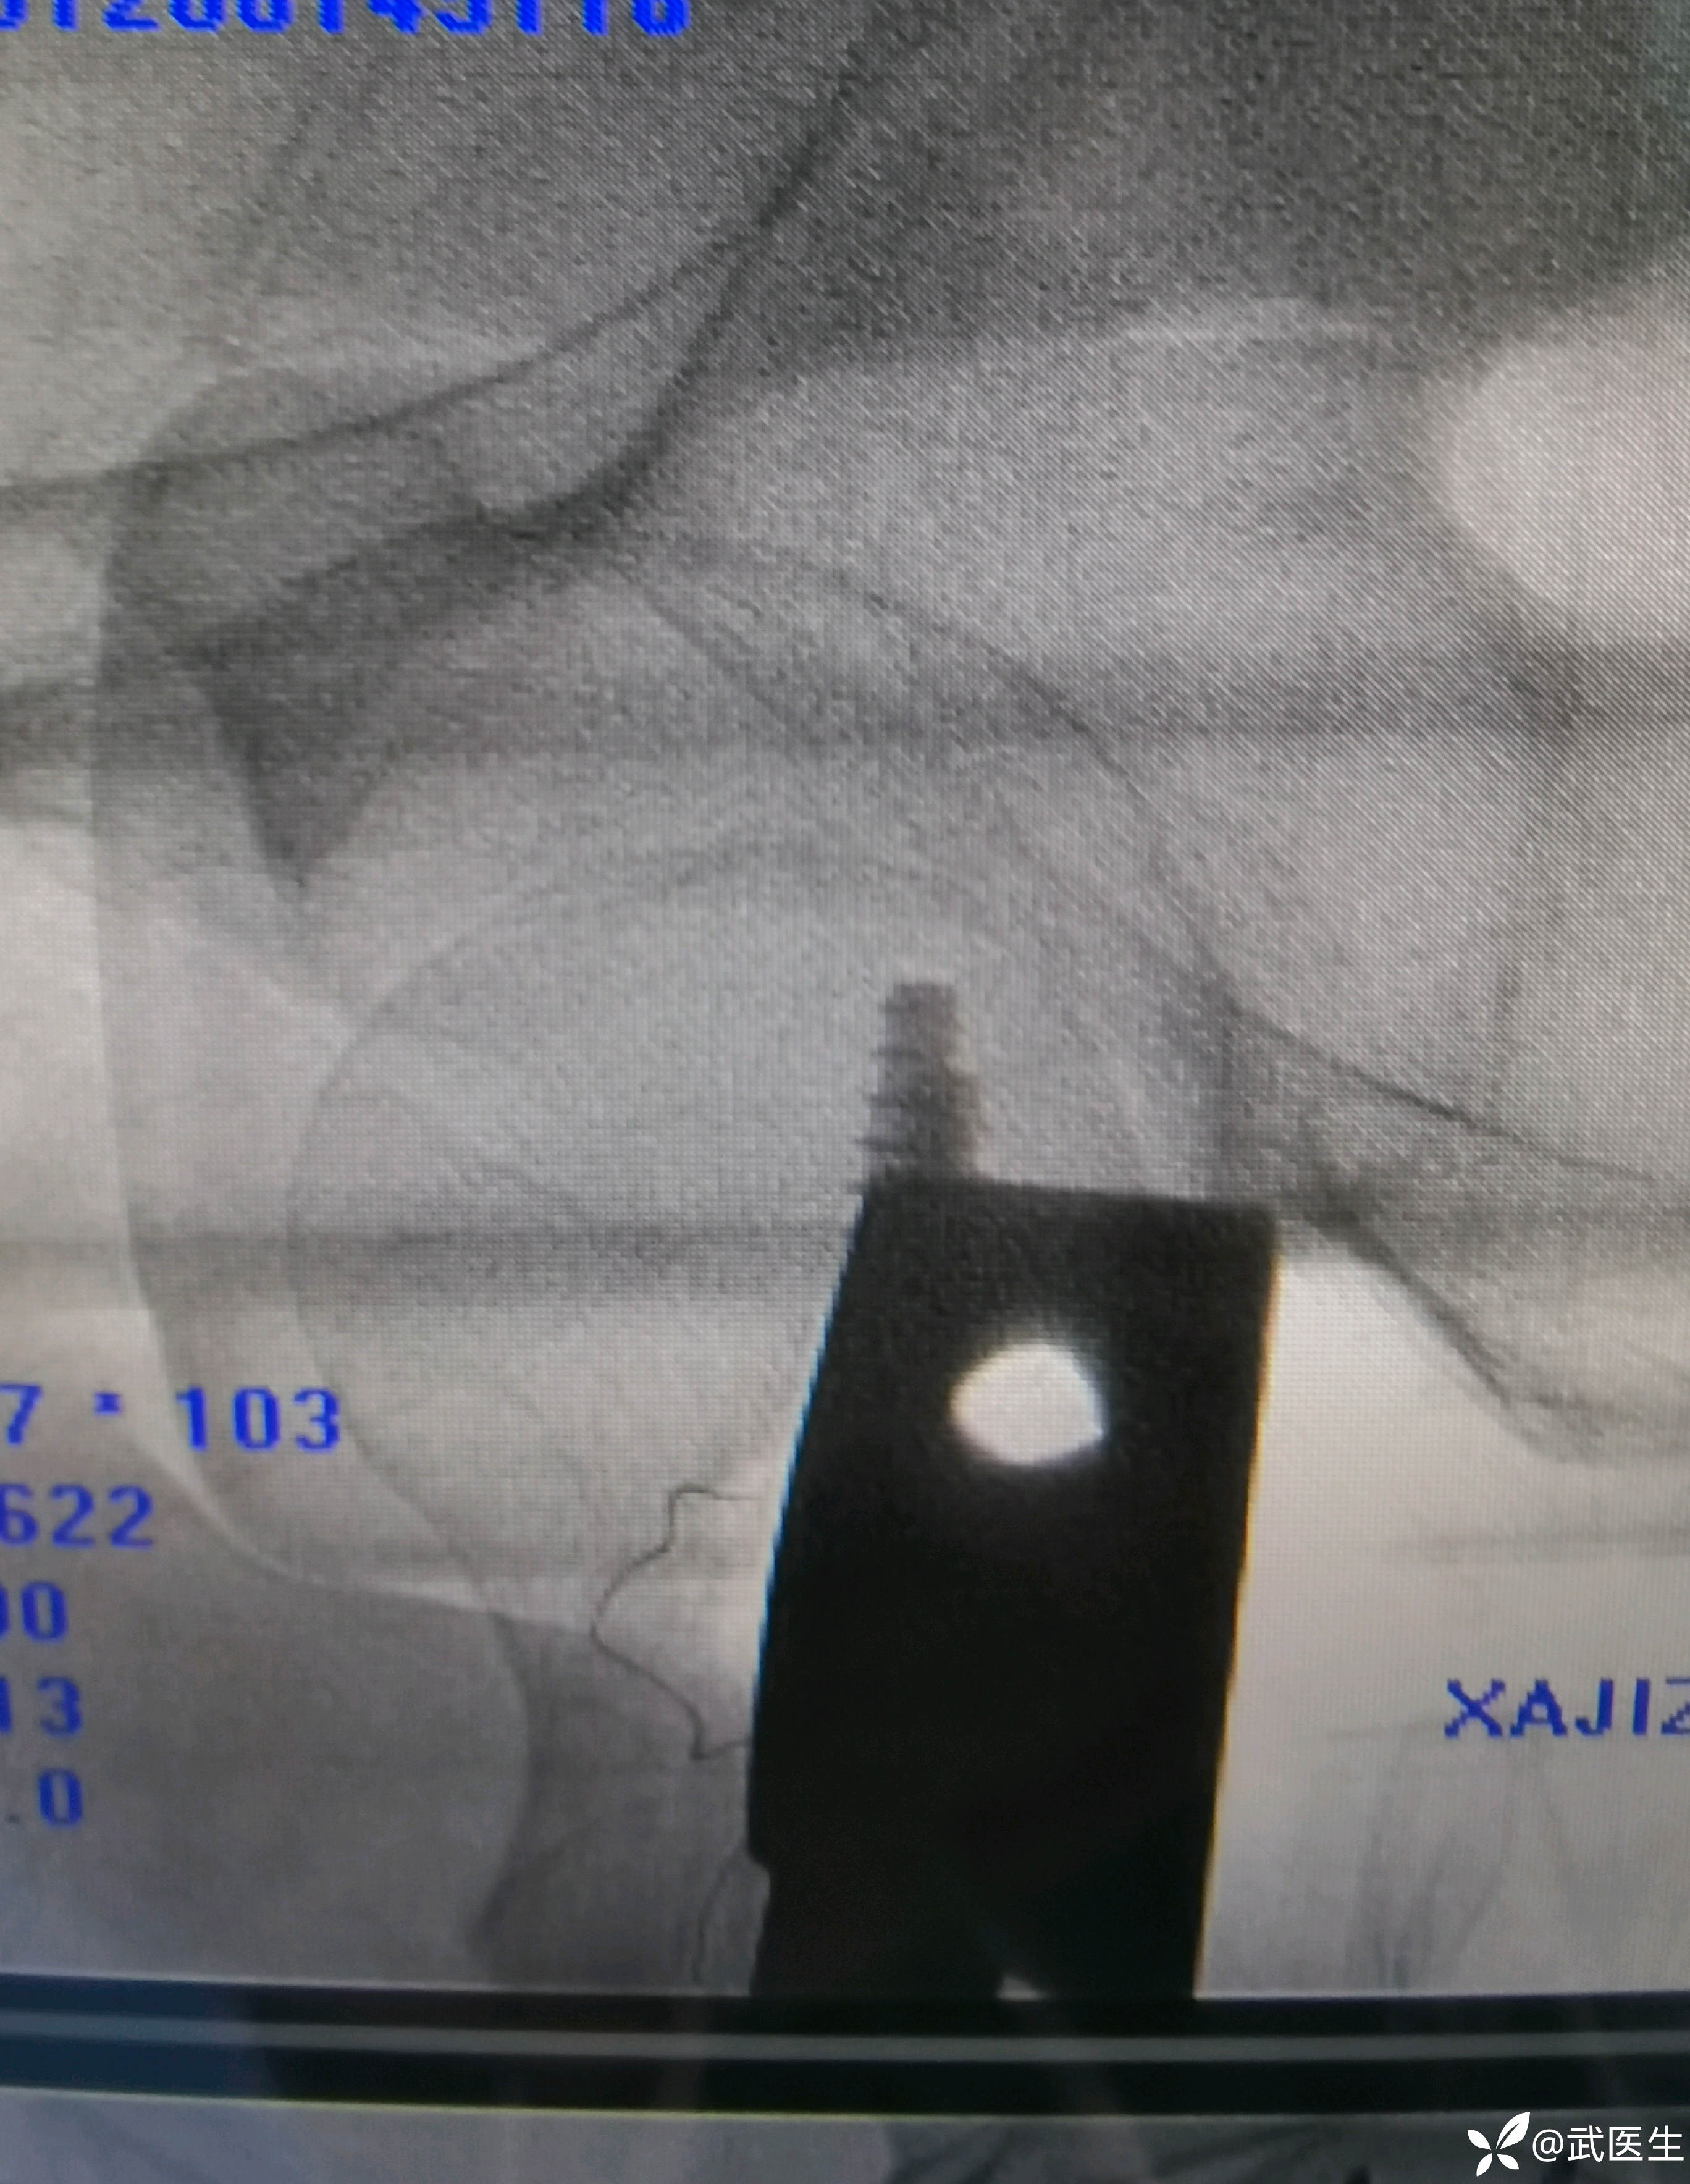

正位头颈螺钉位置良好

轴位🙄

偏后这么多,唉,不过手感有劲,没打空,就不再犯“强迫症”

两道钛缆吧,又怕疼,要求又高,片子还是要好看些